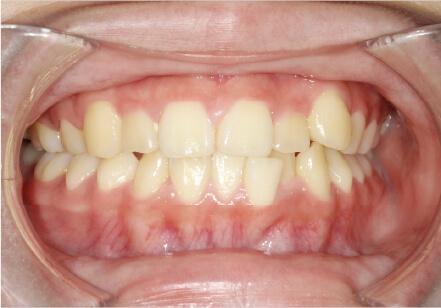

叢生の症例

17歳

/

女性

相談内容

カウンセリング・診断結果

治療内容・方法

全額アライナー矯正

術後の経過・現在の様子

クリアライナー使用

治療のリスク

痛み・歯根吸収・歯肉退縮・虫歯・後戻り

費用・治療期間

715,000円、2年10ヶ月

トレーニングなど